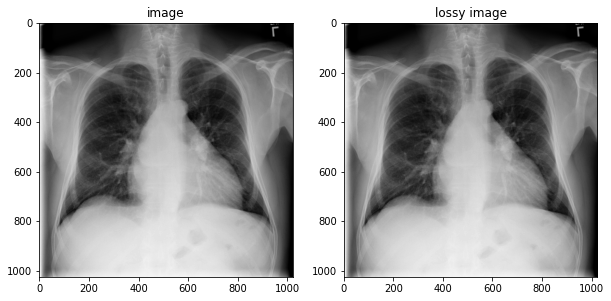

image = tfio.image.decode_dicom_image(image_bytes, dtype=tf.uint16)

lossy_image = tfio.image.decode_dicom_image(image_bytes, scale='auto', on_error='lossy', dtype=tf.uint8)

fig, axes = plt.subplots(1,2, figsize=(10,10))

axes[0].imshow(np.squeeze(image.numpy()), cmap='gray')

axes[0].set_title('image')

axes[1].imshow(np.squeeze(lossy_image.numpy()), cmap='gray')

axes[1].set_title('lossy image');